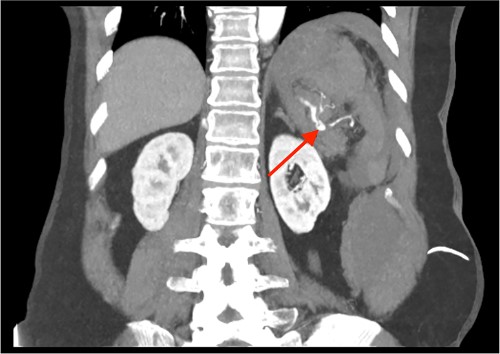

Triple-phase computed tomography (CT) of the abdomen and pelvis revealed a sizeable acute haematoma in the left upper abdomen, below the gastric fundus and body, alongside the pancreatic tail and splenic hilum, extending amongst the proximal small bowel mesentery and into the left subphrenic space. The origin of the haemorrhage appeared to arise from the left upper quadrant. There was a pseudoaneurysm in close proximity to the pancreatic tail and splenic hilum, apparently arising from the adjacent distal splenic artery. CT scan did show local contrast extravasation into the haematoma, as mentioned above (Figs 1–3).

CT of the abdomen and pelvis, coronal plane, arterial phase. Large intraabdominal haematoma in the left upper quadrant.

CT of the abdomen and pelvis, coronal plane, arterial phase. Contrast extravasation from the ruptured SAP.